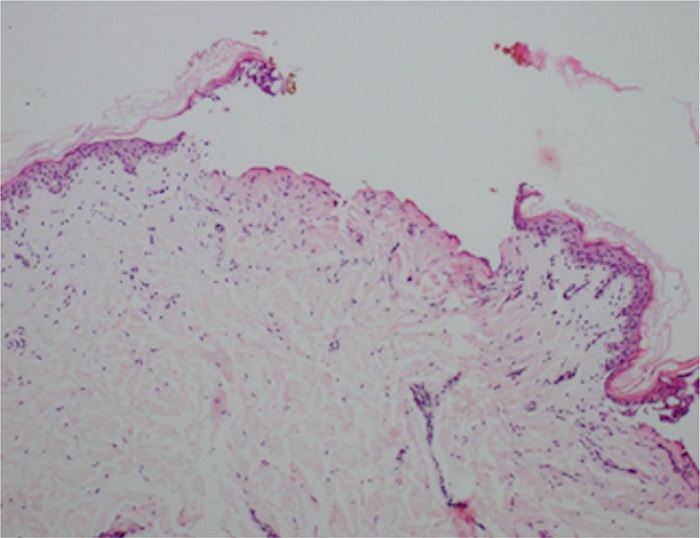

A análise histopatológica da área A (Figura 1), que foi submetida a PBT, apresentou um trecho central de figuração com 0,6 mm de diâmetro e profundidade de 0,15 a 0,25 mm. A profundidade foi medida sem considerar a epiderme. A derme papilar ao redor da área descrita apresenta edema com redução da quantidade de tecido elástico, o que foi confirmado pela coloração de Verhoeff. A coloração de Tricrômio de Masson não levou a achados específicos.